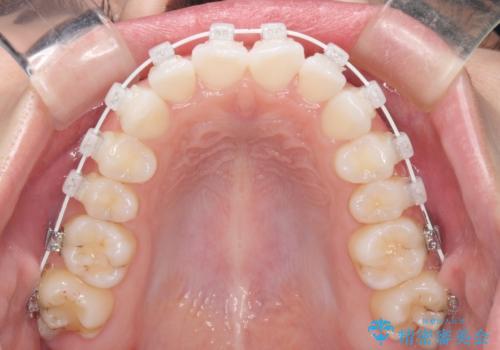

- 矯正装置

- 審美装置

- 海外留学を前に上下のデコボコと奥歯の咬み合わせを改善したいとのことで来院された患者様です。

期間が限られていたため、ワイヤー装置による矯正治療を行うこととしました。

治療開始から4ヶ月ほどで概ね歯列が整い、その後の3ヶ月で細かい部分を仕上げていきました。

短期間で綺麗に仕上がり、患者様には大変満足していただきました。